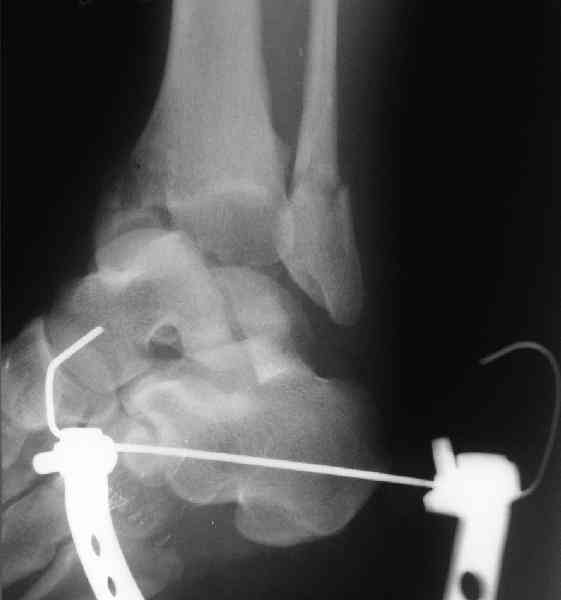

Interesting case

The ankle joint looks ruined. I wonder howcome is it as ruined after 2 days. I would open the joint( Some people would artroscope it) and judge the osteosynthes vs ankle fusion according to the ankle joint condition. The subtalar does not look injured, but if you feel there is a clinical

problem- CT it. Above all- when I see such an X-Ray I call the resident who ordered it and tell him that I would expect him first thing to reduce it on arrival since the soft tissue suffer and I hope that currently the p-nt is reduced to some extent at least.

Sorry- I revised it and the talus is fractured- take him to the theater at once and reduse it with Int Fix

The soft tissue will be a problem- Ex Fix will be better thn plaster

а основании двух видов ренгенограмм невозможно радикально решить о необходимости открытой репозиции или первичного артродеза.

Для оценки состояния нужны дополнительные исследования, например Canale или Broden ренгенограммы и Компьютерная томография.

При переломах тарана всегда имеется риск AVN, а классификация Hawkins поможет разобраться с предполагаемыми осложнениями.

Если в первом типе, когда перелом шейки без смещения, тогда AVN менее 10%, при втором типе когда имеется смещение и вывих тарана в субталарном сочленении меньше 40%, а при типе III когда смещение в голеностопном и субталарном суставах - около 90% и в типе IV, когда происходит полный вывих, риск AVN достигает 100%.